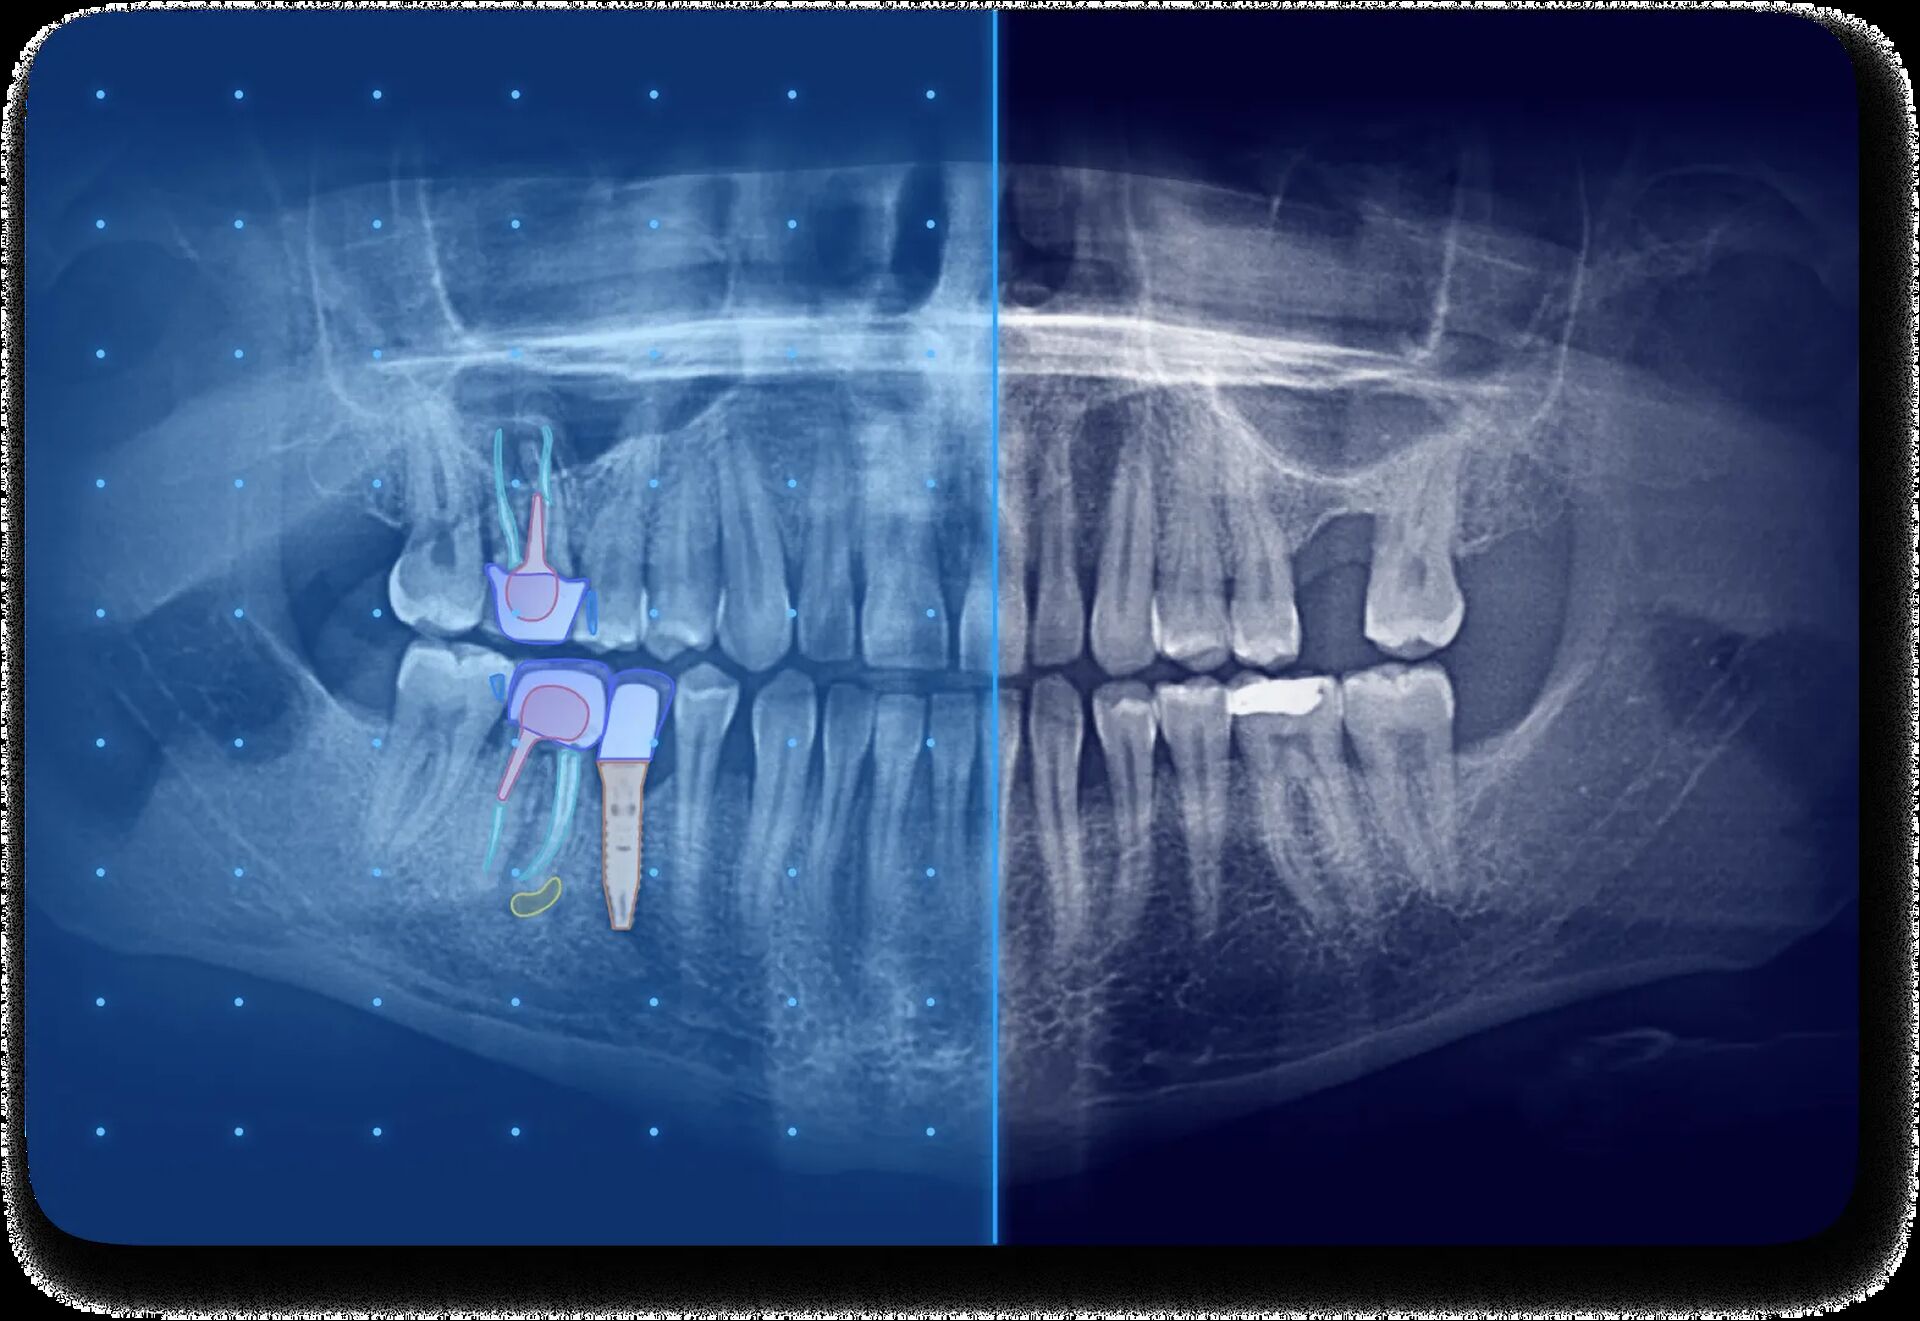

L’intelligence artificielle (IA) s’impose progressivement dans la dentisterie, transformant tant le diagnostic que la relation patient-praticien. En imagerie par exemple, l’IA permet de détecter automatiquement des anomalies sur des radiographies panoramiques ou CBCT, améliorant la sensibilité et la spécificité des diagnostics, limitant ainsi la variabilité des interprétations entre praticiens. Elle contribue aussi à fluidifier le pilotage du cabinet dentaire en analysant les données patients, les paramètres d’activité et les devis, ce qui offre une vision anticipée de la productivité et de la rentabilité.

La communication patient est un autre champ clé : grâce à des outils visuels basés sur l’IA, les éléments pathologiques sont mis en évidence par des codes couleur, des schémas explicatifs et des rapports pédagogiques. Résultat : les patients comprennent mieux leur situation, adhèrent davantage aux traitements proposés et sont ainsi plus engagés. Cela se traduit par une augmentation notable du taux d’acceptation des plans de traitement.

Allisone est une solution logicielle basée sur l’intelligence artificielle conçue pour accompagner les praticiens dentaires dans leur communication avec les patients, leur planification et leur diagnostic. Grâce à une interface intuitive, elle permet de mettre en évidence les repères radiographiques à l’aide de codes couleur et d’illustrations pédagogiques, facilitant ainsi la compréhension des images par les patients et renforçant leur confiance dans les soins proposés.